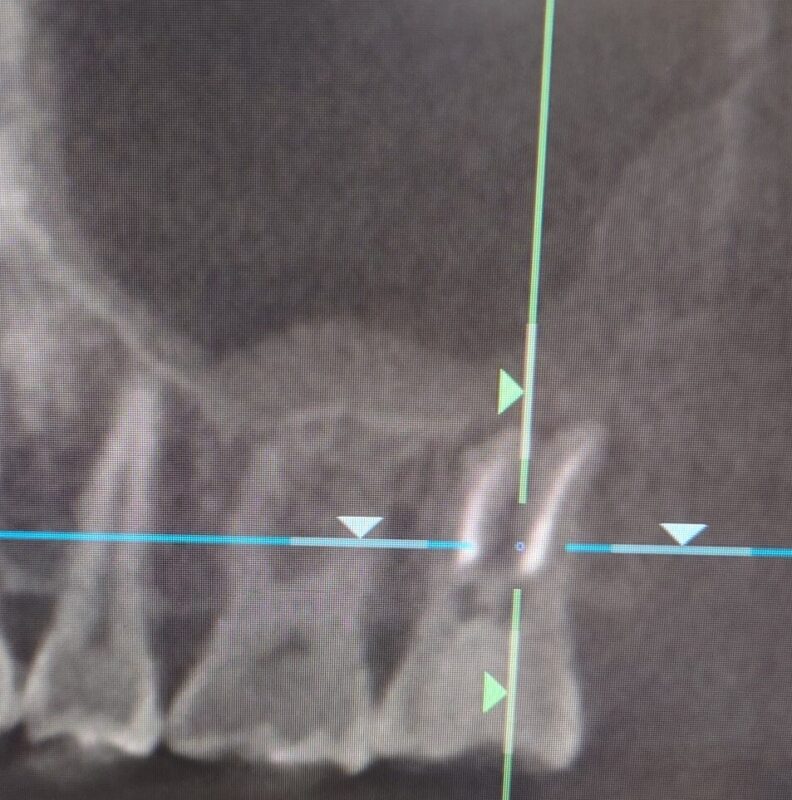

ただ 高度な技術を要する精密根管治療を行えば歯性上顎洞炎は治る可能性はあります

術前 一番奥の歯の根の先に影 上顎洞内は白濁して映っています